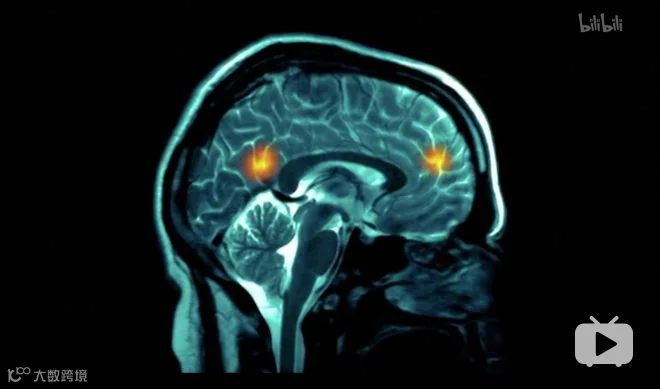

精神学家安德烈·巴特尔在许多热恋情侣中做过一个这样的实验:

让他们看着自己伴侣的照片,同时扫描这些实验者的脑部。

扫描的结果显示,每一位处于热恋期的人,在看到自己伴侣的照片时,脑部的奖励区域都异常活跃。

意思是此时的大脑会分泌大量让我们感到快乐的化学物质。

这也解释了为什么爱情会让人感受到幸福和快乐,刚刚在一起的时候,彼此都愿意粘着对方。

但是,此时大脑中一些相对理性、做出判断的理性区域,却是被压抑的。